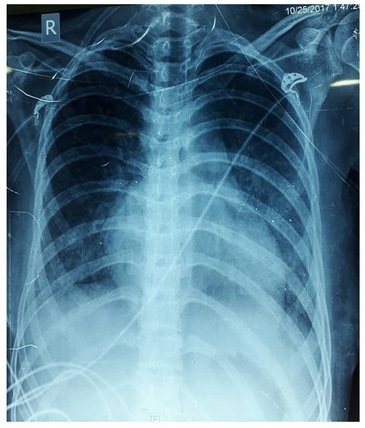

X-ray